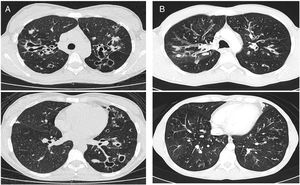

The Bhalla score evaluates the severity of bronchiectasis, peribronchial thickening, extension of bronchiectasis (number of pulmonary segments), extension of mucus plugging, sacculations and abscesses, involvement of bronchial generations, number of bullae, emphysema, and collapse/consolidation. Instead of assessing emphysema and its extension, we evaluated the extent of air trapping in the expiratory sections (Table 1). The points in each category vary from 0 to 3. The sum of the score obtained for each item was subtracted from 25 in order to obtain the overall Bhalla score. Different examples of Bhalla scores are shown in Fig. 1.7

Axial CT images of pulmonary window in different patients with CF and different Bhalla scores. Bhalla 23 is an example of a mild disease with mild bronchiectasis while Bhalla 16 presents a moderate disease with mucous plugging and bigger bronchiectasis. Finally, Bhalla 10 shows a severe disease with sacculations, greater thickness wall and higher luminal diameter of bronchiectasis, also with mucous plugging and air trapping.